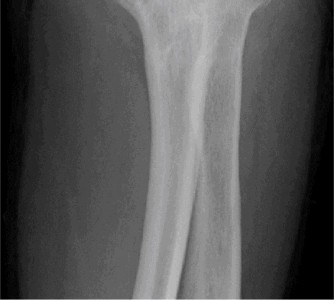

Surgically treat a patient with glenohumeral rheumatoid arthritis? Perioperatively manage a patient with glenohumeral rheumatoid arthritis? CASE 19 Dr. Anna Cohen-Rosenblum A 45-year-old, left-hand-dominant male with a history of Crohn’s disease presents to your clinic complaining of left shoulder pain for the past 2 months. He is unable to localize the pain but says it is worse with overhead motion and radiates to his elbow. He was diagnosed with Crohn’s at age 20 and his symptoms are currently under fairly good control with etanercept, but he has had multiple flares in the past treated with courses of IV and PO steroids. He notes a history of traumatic left shoulder dislocation while playing high-school football but denies any subsequent dislocations or shoulder pain prior to 2 months ago. Physical examination is significant for pain with active abduction and forward flexion of the left shoulder. Imaging is shown in Figure 2–53.

Figure 2–53

What is the most appropriate next step?

The correct answer is (A). In a patient with IBD and a history of steroid use, avascular necrosis (AVN) should be at the top of the differential diagnosis. Other risk factors for AVN of the humeral head include a history of trauma, chemo/radiation, Caisson disease, sickle cell disease, alcohol abuse, SLE, pregnancy, and tobacco use. The patient has x-rays with sclerotic changes suspicious for AVN, therefore MRI is the best next step for this patient. CT of the left shoulder (Answer B) would not show any of the bony edema that characterizes early AVN. PET scans (Answer C) can also be used to identify early AVN but have been shown to be less accurate than MRI. D is incorrect because AVN is a higher likelihood for this patient than glenohumeral arthritis or a labral tear and therefore should be investigated first with MRI.

MRI of the right shoulder is shown in Figure 2–54. What is the diagnosis?

The correct answer is (B). The MRI shows bony edema consistent with avascular necrosis of the humeral head, which combined with the sclerotic radiographic changes shown in Figure 2–54, classify him as stage II in the Ficat classification. Although the Ficat classification was designed for AVN of the femoral head, it is also commonly used to classify AVN of the humeral head. Table 2–7 shows the Ficat classification stages I to IV. Different modifications of the Ficat classification exist as well, including the Steinberg and Cruess. Choices C and D are incorrect because they all are characterized by radiographic changes of varying degrees (such as osteolytic lesions, subchondral collapse, and osteoarthritis), which this patient does not have.